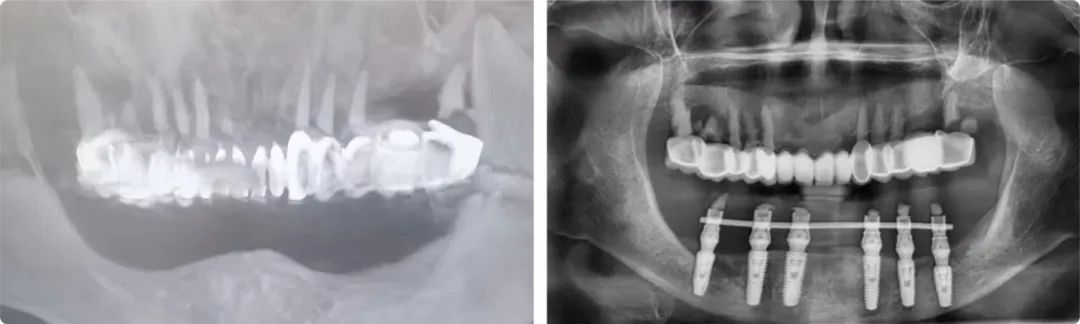

“患者牙槽骨的垂直高度太低,牙槽嵴高度不足9毫米,直接種植會(huì)傷及神經(jīng),首選方案是先做骨增量手術(shù)再種植,但她的情況根本做不了骨增量,只能選擇高風(fēng)險(xiǎn)的第二方案:先行雙側(cè)下頜神經(jīng)游離術(shù),通過(guò)手術(shù)把左右兩側(cè)的下頜神經(jīng)撥到安全位置,再做種植。”

患者術(shù)前術(shù)后檢查報(bào)告

老人和家屬非常信任姜辰,接受了這個(gè)方案。術(shù)中植入了6枚植體,術(shù)后即刻修復(fù)完成戴牙,老人的咀嚼功能當(dāng)天恢復(fù)。